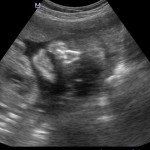

Con l’ecografia transvaginale è possibile vedere dopo circa 3 settimane dal concepimento la camera gestazionale nella cavità uterina. Successivamente è possibile visualizzare l’embrione (3-5 mm.) a circa 6 settimane dall’ultima mestruazione (4 settimane dal concepimento) ed a questo periodo è già visibile l’attività cardiaca fetale Anche i primi dettagli sulla morfologia fetale (polo cefalico, abbozzi degli arti) sono visualizzabili più precocemente con l’ecografia transvaginale, risultando essi visibili intorno a 8-9 settimane.

Con l’ecografia dei primi mesi di gravidanza, si può anche valutare la normalità dell’utero (eventuale presenza di fibromi già preesistenti alla gravidanza) e delle ovaie.